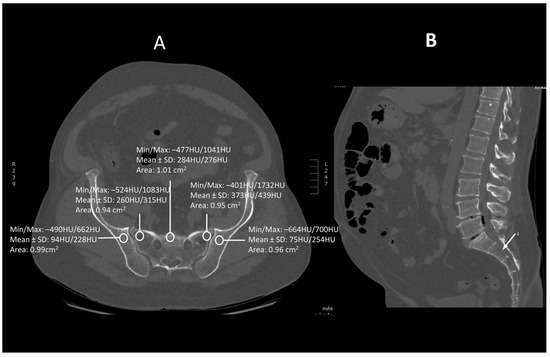

Figure 1.

A transverse (A) and saggital (B) projection of CT scan in level S1. A circular region of interest (ROI) ranging from 0.8 to 1.2 cm2 has been placed at the ala of the ilium, the wing of the sacrum and the body of sacral vertebra 1.

Images were viewed using the bone algorithm default windows. The investigator first determined axial images in levels of mid-lengths of bodies of sacral vertebrae 1, 2 and 3 that afterward were confirmed by coronal and sagittal reconstructions (Figure 1, Figure 2 and Figure 3). The volumetric bone density expressed in HU values was measured in sacral levels of S1, S2 and S3. Apart from the bodies of sacral vertebrae S1–S3, the measurements involved the ala of the ilium in the vicinity of the sacroiliac joint and the wing of the sacrum. All the measurements were performed on the pathway of presumptive iliosacral screws to stabilize the sacroiliac joint.

In order to standardize measurements while accounting for normal anatomic variations and optimum iliosacral screw trajectories—so as to avoid injuries of neurovascular structures—standardized circular voxel regions of interest (ROIs) were drawn (Figure 1, Figure 2 and Figure 3) [12]. As presented in the former studies, these ROIs were drawn in levels of mid-lengths of the bodies of sacral vertebrae 1, 2 and 3, the right and left wings of sacrum and the ala of the ilium in sacral levels of S1–S3 [13]. The aforementioned standardized ROIs were drawn with areas ranging from 0.8 to 1.2 cm2. This range of area was estimated as it best represented the osseous surface area, which is required to safely place 7.0–mm iliosacral or transsacral screws [4].